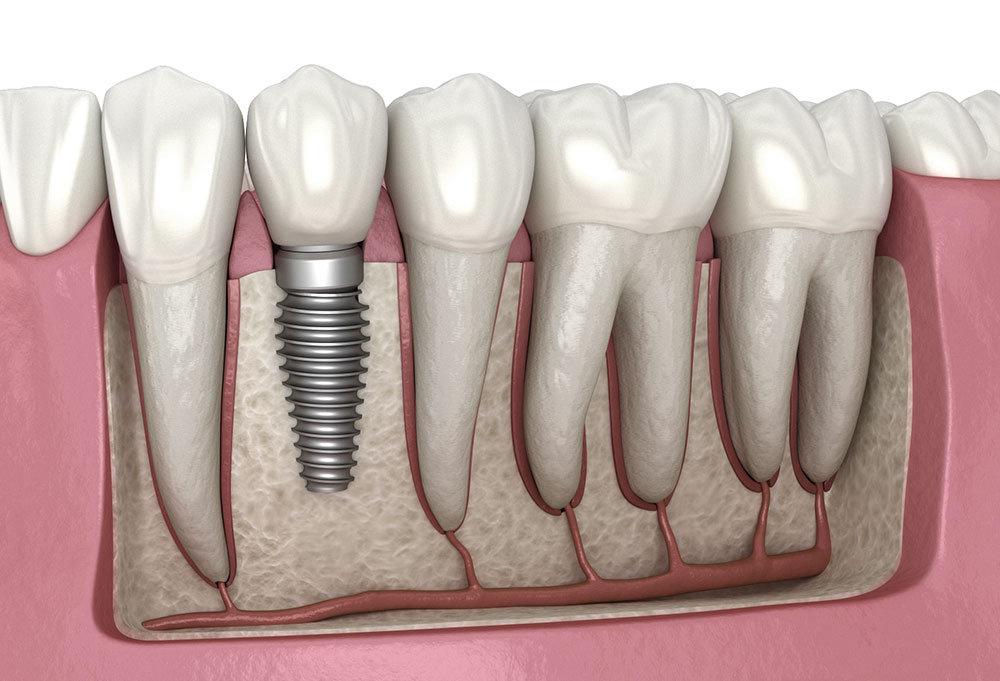

A single dental implant is the ideal solution when one tooth is missing or damaged beyond repair. The implant consists of a titanium post that is surgically placed into the jawbone, where it fuses naturally with the surrounding bone over several months. Once healed, a custom porcelain crown is attached to the post, creating a restoration that looks, feels, and functions just like a natural tooth. Unlike a traditional bridge, a single implant does not require altering the adjacent healthy teeth, making it the most conservative and long-lasting replacement option available.